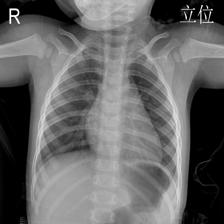

To pre-train a high-performance X-ray foundation model, the first thing we need to do is the collection of large-scale X-ray images. Therefore, a large-scale and high-resolution dataset that contains X-ray medical images is collected for the pre-training. Some representative samples are visualized in Fig. 3.